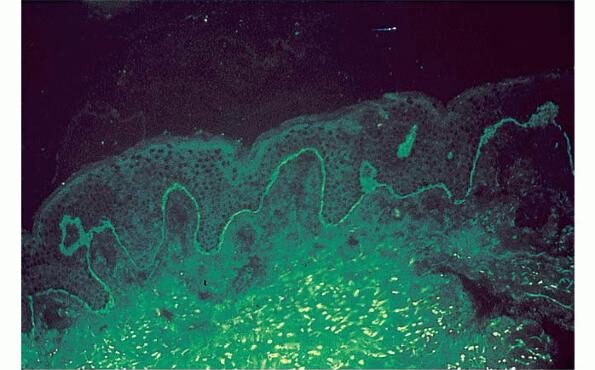

Parapsoriasis Large-plaque = نظير الصدف كبير اللويحات Parapsoriasis There are three entities described as parapsoriasis: small-plaque parapsoriasis, large-plaque parapsoriasis, and parapsoriasis variegata. Large-plaque parapsoriasis and parapsoriasis variegata are best considered as early stages of cutaneous T-cell lymphoma/mycosis fungoides. The small-plaque parapsoriasis is also known as xanthoerythrodermia perstans of Crocker and as digitate dermatosis . Pink-to-yellow, slightly scaly, oval or elongated, […]